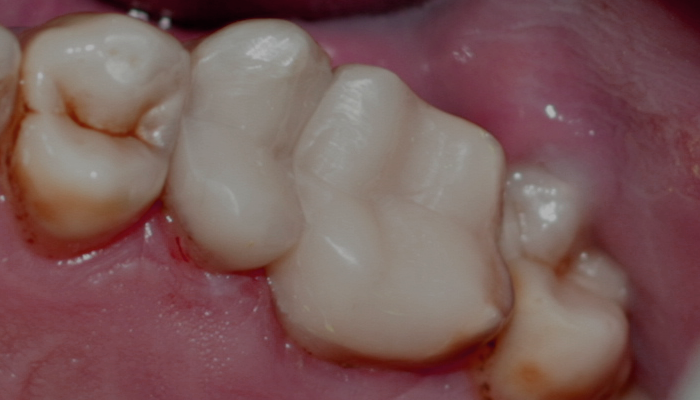

Ендодонтията е раздел от съвременната дентална медицина, който раздел изучава физиологията и патологията на вътрешната част на зъба - пулпна кухина и коренови канали. Названието на раздела идва от старогръцки - ендос - представка за вътрешност и одонтос - зъб. Това е една от научните дисциплини, които претърпяха голямо развитие през последното деситилетие.